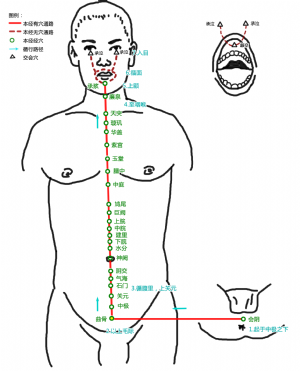

曲骨爲經穴名(Qūgǔ CV2,RN2)[2]。出《鍼灸甲乙經》。別名尿胞(《備急千金要方》),回骨(《銅人腧穴鍼灸圖經》),屈骨(《備急千金要方》),屈骨端(《備急千金要方》)。屬任脈[3][3]。曲骨是足厥陰肝經、任脈的交會穴[3][3]。曲骨指恥骨,此穴在恥骨聯合上緣,故名曲骨[3]。曲骨穴主治小腹、泌尿及生殖系統等疾患:如小腹脹滿疼痛,疝氣,小便淋瀝,遺精,陽痿,早泄,月經不調,痛經,小腹疼痛,帶下,遺尿,尿閉,赤白帶下,不孕,小便不利,癃閉,陰癢,少腹脹滿,水腫,癲疾,五臟虛弱,虛乏冷極,現代又用曲骨穴治療膀胱炎,尿失禁,尿瀦留,睾丸炎,前列腺炎,陰囊溼疹,子宮內膜炎,宮頸糜爛,產後宮縮不全,子宮脫垂,膀胱炎,產後子宮收縮不全等。

標準定位:曲骨穴在下腹部,當前正中線上,恥骨聯合上緣的中點處[6]。

曲骨穴位於腹正中線,臍下5寸,恥骨聯合上緣上方凹陷處[6]。

曲骨穴位於下腹部,當前正中線上,恥骨聯合上緣。仰臥取穴[6]。

曲骨穴在下腹部的位置

曲骨穴在下腹部的位置